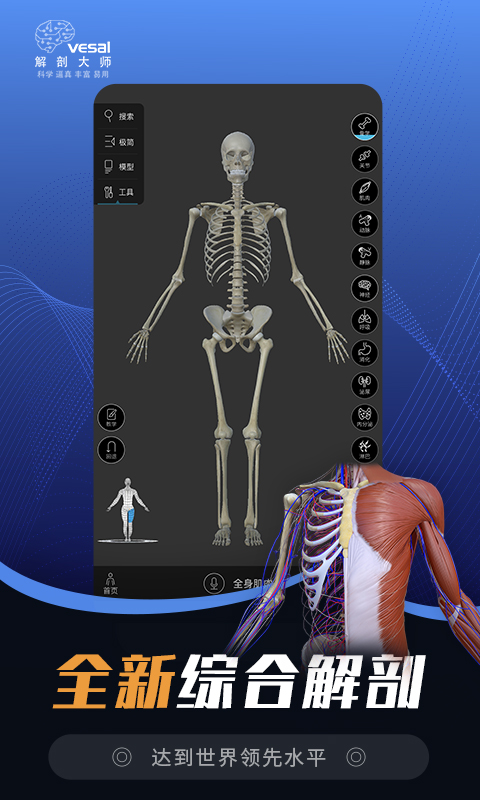

解剖大师介绍

解剖大师3d运动康复图库(Master Of Anatomy‘2024’)是一款解剖学习、患教工具、治疗方案为一体的解剖医学临床指南工具.功能包含AI智能体态评估、3d人体解剖、运动解剖、中医针灸学、康复、疼痛处理、自由脊柱等模块;是专为医疗运动康复从业者打造的3D人体解剖学图谱资源平台.适合运动康复医师 ,医生护士,孕产护理师,普拉提瑜伽教练,中医养生,针灸理疗师,推拿正骨师,健身私练,职业健康培训教练使用.

应用亮点:

解剖,患教,治疗三大模块,强大3D医学教育资源库

一键搜索人体解剖结构,随身康复医学百科宝典

一、解剖模块

——3d人体—— 解剖学三维图谱

男女整体人、微观解剖(细胞cell body)动画资源库、自由脊柱(根据患者脊柱情况,自行操控脊柱模型)